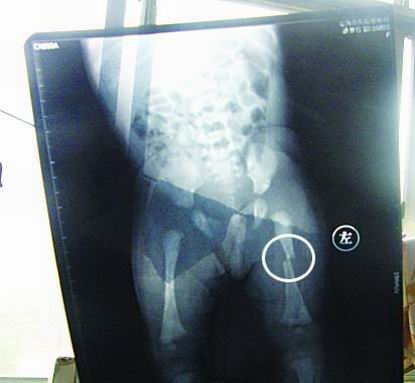

CT显示小梦竹左下肢骨折

今年7月2日下午,定陶县南王店乡沈庄村孕妇聂元真,在定陶县人民医院剖腹产下一女婴,取名为潘梦竹。医院说,婴儿出生后窒息,诊断为新生儿缺血缺氧性脑病,头皮血肿。当晚发现女婴左下肢部位异常,第二天拍片显示为左下肢骨干骨折。7月3日,潘梦竹的头颅CT显示其头顶部骨折,蛛网膜下腔出血,颅内血肿。